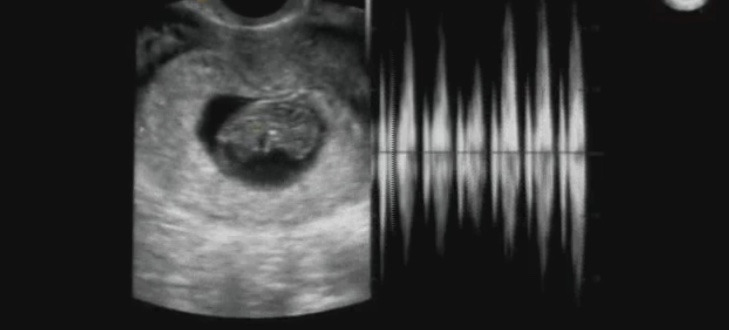

img.jpg

임신 9주차의 태아와 심장 박동의 세기와 간격이다. 탯줄이 형성되고 있고 팔과 다리가 보이기 시작한다. 조금씩 꼬물거리는 게 참 귀엽다. 3cm 남짓의 크기를 하고 엄마 배에서 힘차게 숨 쉬고, 또 자라고 있다니. 실감이 나지 않지만 사실이기에 그저 놀라울 뿐이다. 부모가 되는 경험은 위대한 창조의 섭리에 한 발 더 다가가는 것이다. 아내야, 아가야 고맙다.